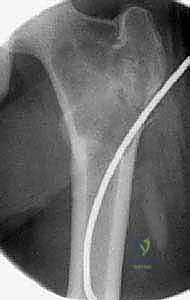

تُظهر هذه الأشعة السينية (X-ray) كيس عظم أحادي الغرفة (UBC) في الجزء العلوي من عظم العضد. لاحظ كيف أن الكيس يسبب ترققاً في قشرة العظم دون أن يخترقها.

- في الـ UBC، تظهر الآفة كمنطقة شفافة (سوداء) مركزية داخل العظم. وهناك علامة مميزة تُسمى "علامة الورقة المتساقطة" (Fallen Leaf Sign)، حيث تسقط قطعة صغيرة من قشرة العظم المكسورة داخل الكيس المملوء بالسائل، وهي علامة مؤكدة بنسبة 100% تقريباً على الـ UBC.